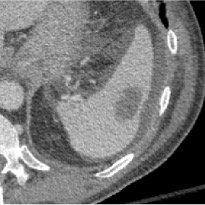

Early tumor detection save lives. Each year, more than 300 million computed tomography (CT) scans are performed worldwide, offering a vast opportunity for effective cancer screening. However, detecting small or early-stage tumors on these CT scans remains challenging, even for experts. Artificial intelligence (AI) models can assist by highlighting suspicious regions, but training such models typically requires extensive tumor masks--detailed, voxel-wise outlines of tumors manually drawn by radiologists. Drawing these masks is costly, requiring years of effort and millions of dollars. In contrast, nearly every CT scan in clinical practice is already accompanied by medical reports describing the tumor's size, number, appearance, and sometimes, pathology results--information that is rich, abundant, and often underutilized for AI training. We introduce R-Super, which trains AI to segment tumors that match their descriptions in medical reports. This approach scales AI training with large collections of readily available medical reports, substantially reducing the need for manually drawn tumor masks. When trained on 101,654 reports, AI models achieved performance comparable to those trained on 723 masks. Combining reports and masks further improved sensitivity by +13% and specificity by +8%, surpassing radiologists in detecting five of the seven tumor types. Notably, R-Super enabled segmentation of tumors in the spleen, gallbladder, prostate, bladder, uterus, and esophagus, for which no public masks or AI models previously existed. This study challenges the long-held belief that large-scale, labor-intensive tumor mask creation is indispensable, establishing a scalable and accessible path toward early detection across diverse tumor types. We plan to release our trained models, code, and dataset at https://github.com/MrGiovanni/R-Super